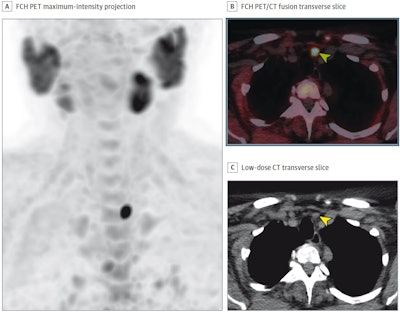

(A) FCH-PET maximum-intensity projection; (B) FCH-PET/CT fusion transverse slice; and (C) low-dose CT transverse slice, showing high FCH uptake in an 11-mm left inferior parathyroid adenoma (arrowheads). The patient underwent minimally invasive parathyroidectomy, leading to normocalcemia during follow-up. No complications occurred.Image courtesy of JAMA Otolaryngology-Head & Neck Surgery